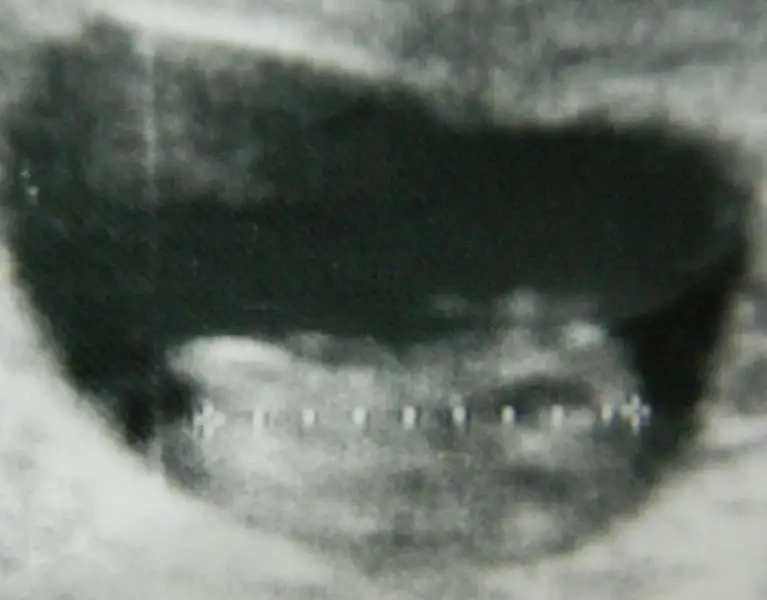

o beyazlık bacak kemiği mi nub mu sizce.haftaya belli olacak cinsiyeti .belli olunca geri dönerim.lütfen yorum yapın teyzeleri

yorum için teşekkürler zeynepzzz.eşim de o kadar dik nub olmaz kemik o demişti.bakalım haftaya öğreniriz inşallah cinsiyetini kız veya erkek sağlıklı olsun da .rabbim herkese nasip eder inşalllah bi evlat